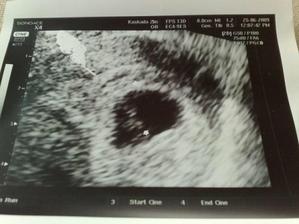

Od poslední operace jsem užívala Utrogestan po něm mi nebylo moc dobře, tak se nasadila Provera.Po ní mám stejně MS nepravidelnou.Koncem května jsme se rozhodli navštívit Car.Chtěli jsme do Zlína, pač to máme blíž, ale moje pojišťovna s nimi nemá slouvu, takže nic.Takže jsme hledali a našli si v Olomouci Fertimed.Objednali jsme se na konzultaci 2.7.2008.Konzultace proběhla bez problému, jen vyšetření, které proběhlo před přítelem bylo pro něj trochu překvapením.Příteli udělali SPG kde zjistily že je v pořadku.Posléze nám byli zjištěny Ureoplazmata, tak jsme s přítelem zobali ATB. Nebylo nám ani jednomu znich dobře. A měli jsme zakázáno snažilkování. 20.8.2008 jsem měla jít na svou první IUI, ale bylo mi zjištěno, že nemám ovulaci.Tak s toho sešlo.9.9.2008 jsem měla vyšetření průchodnosti.12.9.2008 jsem šla na KO a na výsledky.Vše je ok, vše mám průchodný i po všech operacích a ureoplazmatech.A snažilkování opět zakázáno kvůli zahojení.Poprvé mi byly dány stimulace Clostilbegyt.Tak teď už jen čekám na mrchu.Mrcha dorazila 3.10. takže opět smůla,7.10. začínám zobat Clostilbegyt.Po sexíku po něm trochu špinim, ale je to možná ještě brzy kvůli tomu vyšetření průchodnosti. 13.10. jedu do Car na KO hm tak jsem zvědavá jak to na mě zapůsobilo.Uvidíme co budu mít v bříšku 🙂) KO dopadla dobře mám 4 vajíčka o velikosti 1.4cm a sliznici 5.5cm. 17.10.08 v 13hod máme první inseminaci.Po píchnutí pregnylu mi není dobře a ještě k tomu ten divný klobouček co zavádějí.19.10. kontrola a druhá inseminace.29.10. Kontrola v CAr a nalezena další cysta.Další cyklus tedy proběhne bez Clostíku.19.11. kontrola máme ovulaci a 2 folikuly.24.11. třetí inseminace opět je mi špatně po pregnylu a ten klobouček hrůza 26.11. čtvrtá inseminace opět je mi špatně po pregnylu, odebrána krev na tumorové markry,štítnou žlázu a cytologie.5.12. kontrola není nic vidět, krev v pořádku aspoň se nemusím bát že mám v sobě rakovinové buňky,štítná žláza též v pořádku.Cytologie bude po Vánocích.Přes Vánoce nepracují tudíž se budeme snažilkovat doma.Přes Vánoce jsem si zkoušela porvé udělat ovulační testy.Testy mi vycházely // jeden mi vyšel i s /// což bylo tedy opravdu divné.5.1.09 jsem si udělala poslední ovu test s// nu jenže 6.1.09 jsem dostala pěkně silnou MS.12.1.09 jsem byla u své obvoní dr, která mi vzala krev a moč.13.1.09 jsem byla u své gynekoložky a ta mi řekla že jsem měla opět cystu která byla už prasklá.Moje obvodní lékařka mi řekla ,moč je v pořádku,ale v krvi mi chybí červené barvivo v červených krvinkách.Tak jsem si koupila železo s kyselinou listovou.21.1.kontrola v CAR řekli mi že mám 2folikuly, odmítla jsem IVF, a objednala se do FN Olomouc (10.března 11:45) k dr. Dostálovy, výsledky z cytologie dopadly dobře. 10.3. první poradna u doc.Dostála, vše probíhalo v pořádku, zatím jsme jen dotsali papíry na IUI. 23.3. 13dc sliznice 10mm, ovarium vlevo 14+PCO, ovarium vpravo 17mm, 25.3.-27.3. plánovaný styk. 21.4.09 13dc sliznice 10,3mm, vpravo 19x26mm folikl, dnes IUI, následující den plánovaný styk,zavádění Utrogestanu po 8dní. 13.5. poradna s doc. Dostálem, výsledky horm. profilu ok, spg ok, domluva na IVF ( srpen 09 ), dostala jsem veškeré léky a poučení. 18.5. 13dc sliznice 11mm, ovarium vlevo 17mm, vpravo nic, 19.-20.5.09 plánovaný styk.21.5. UTZ sliznice 7,4mm, ovaria 0, 1.6.09 HCG 103,9. 18.6.09 UTZ 6tt embryo s pravidelnou akcí srdeční. 25.6.09 UTZ 7tt vše ok. 9.7.09 UTZ 9tt těhu průkazka. 3.8.09 Prediko UTZ 13tt vše ok jen nemáme změřenou nosní kůstku. 6.8.09 13tt kontrola, 26.8.09 16tt kontrola 1,5kg, 10.9.09 18+1 kontrola 0,5kg, 24.9.09 20+1 kontrola první pohyby 2,5kg, 25.9.09 Prediko UTZ 20+2, 15.10.09 23+1 1,5kg, 2.11.09 test na cukrovku už nikdy v životě!, dietu nedržím ale musím chodit na ko, 5.11.09 26+1 2kg,